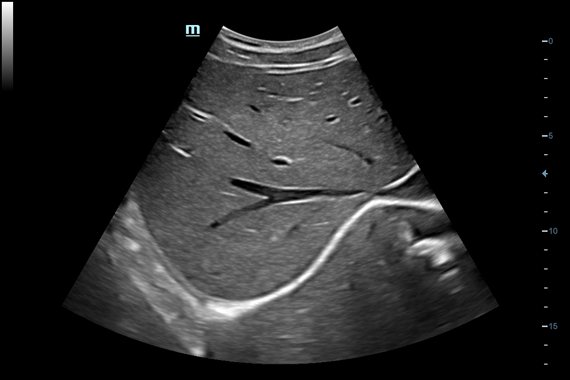

• Поддержка режимов сканирования B/M/Цветовой доплер CDI/Цветной M/Энергетический доплер PD/Направленный энергетический доплер Dir.PD.

• HR Flow - режим отображения кровотока с высоким временным и пространственным разрешением для точной и однородной визуализации сосудов, в том числе самых мелких.

• Vascular package - предустановленные параметры, аннотации, маркеры, программы измерений для ангиологии, включая транскраниальные исследования